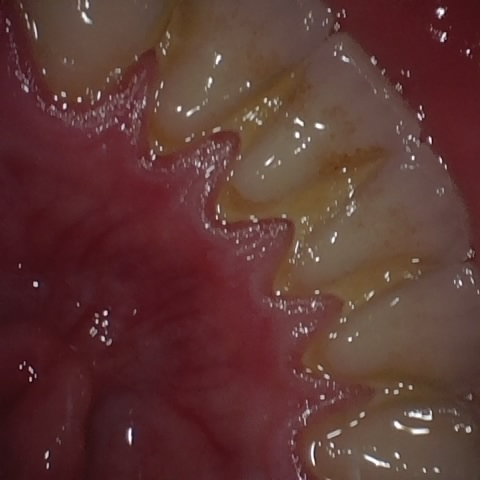

Annotated as "Bad"

Original Image Rendering Image